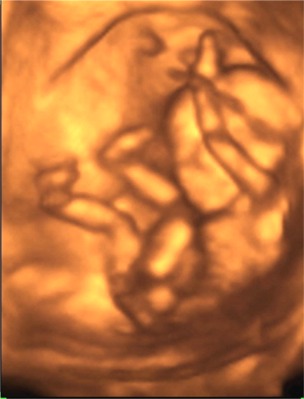

Babucink 14 hetesen és 5 naposan (13 cm és 10,2 dkg)

"Látjátok, milyen ügyesen tornázom?"